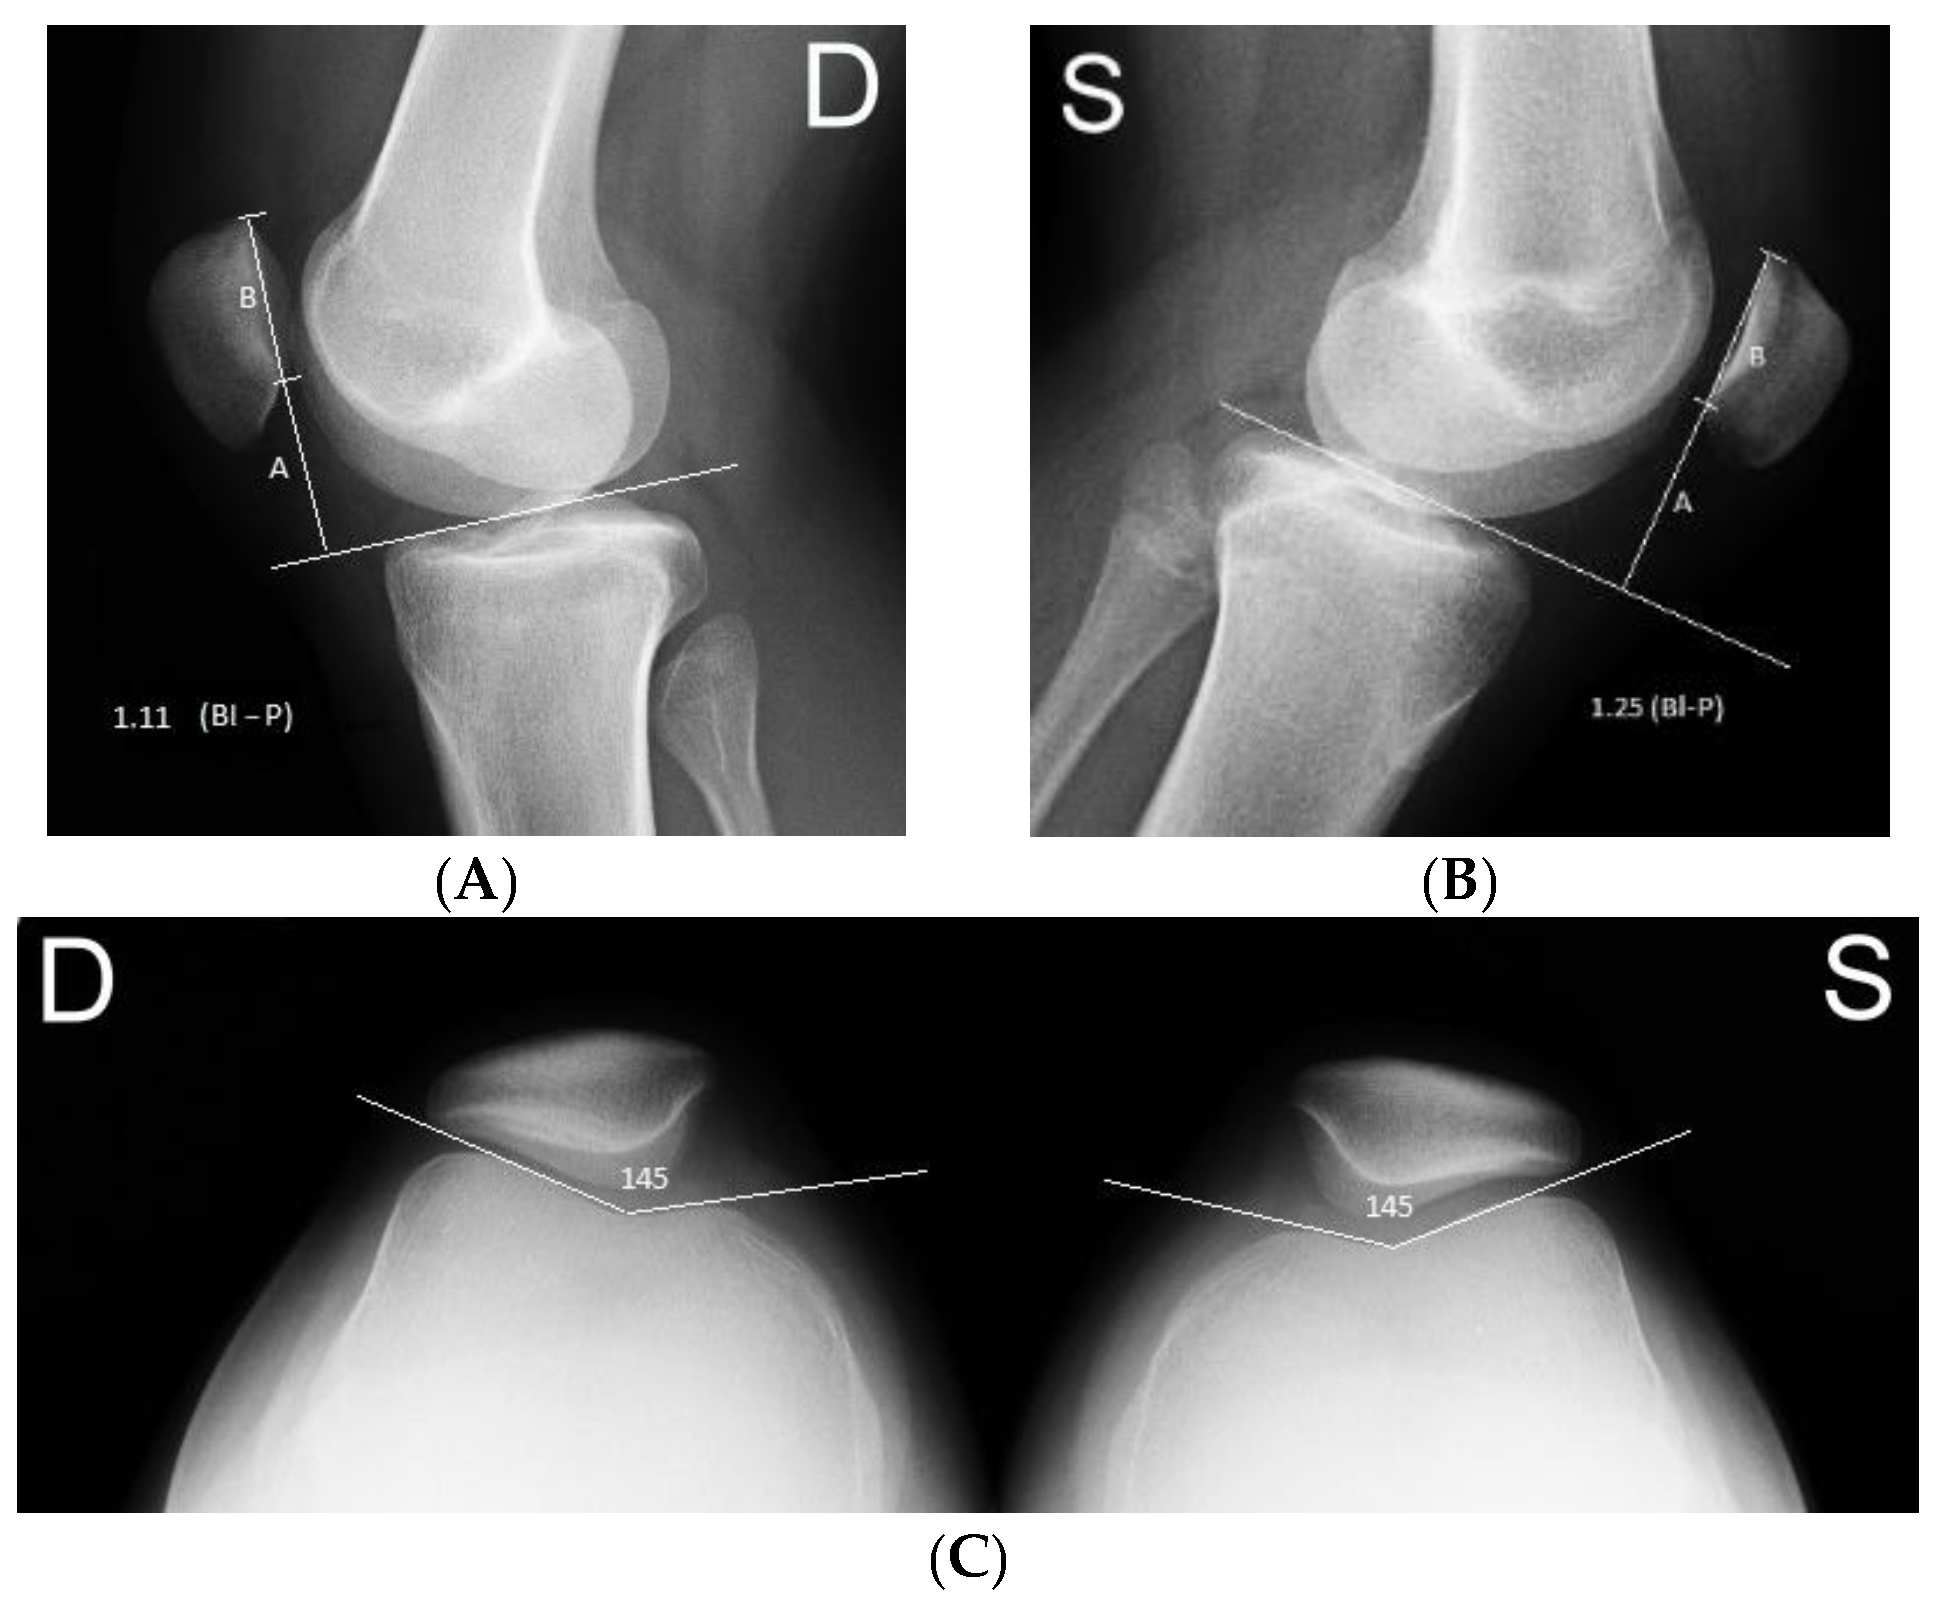

Relieve knee pain effectively with a high-quality patella tendon strap. Designed to provide targeted compression for jumper’s knee, Osgood-Schlatter, and patellar tendonitis, this adjustable support brace stabilizes the kneecap during exercise. Discover how our durable, lightweight strap enhances joint stability, improves comfort during workouts, and accelerates your recovery from common chronic knee injuries.